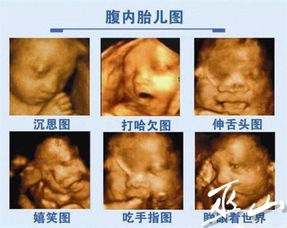

观察胎儿生长发育情况:通过彩超检查,医生可以观察胎儿的头部、四肢、内脏等各个器官的发育情况,确保胎儿在母体内的健康成长。

胎儿四肢:观察胎儿四肢的长度、形态,以及手指、脚趾的发育情况。